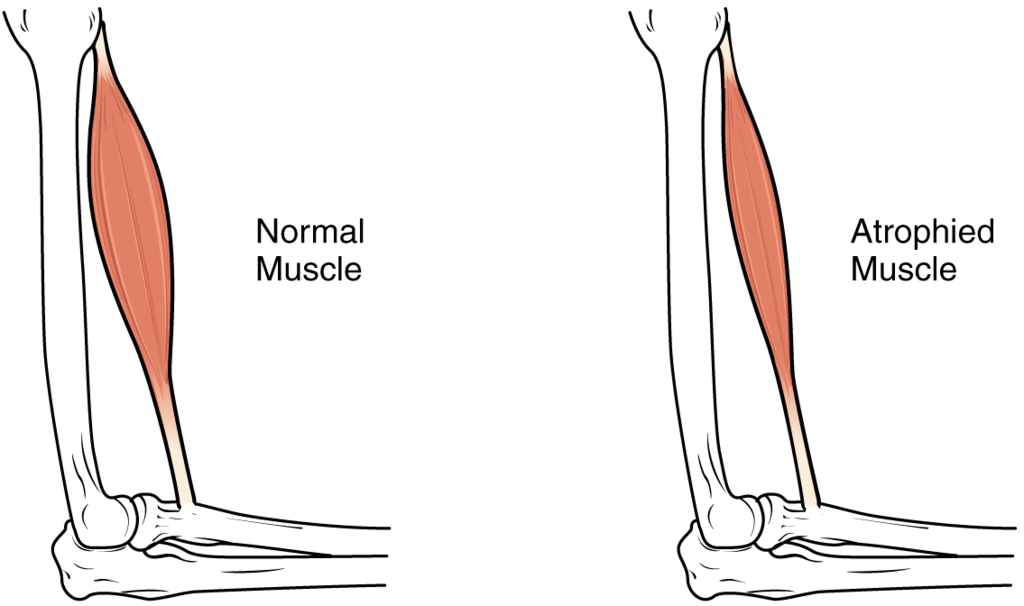

This page is under construction. For now, it is just a resource of the images found in the OpenStax Anatomy and Physiology Handbook. It wil slowly change into a revision tool. Each slide has a number. Use this to refer to the slide. When completed, it will have an unlabelled section, with labelled slides in parallel. On the unlabelled slides, write your answer and use the labelled slide to assess yourself. Keep track by also noting the number on each slide. Improvement at each attempt is important, more so than full marks on a first attempt.